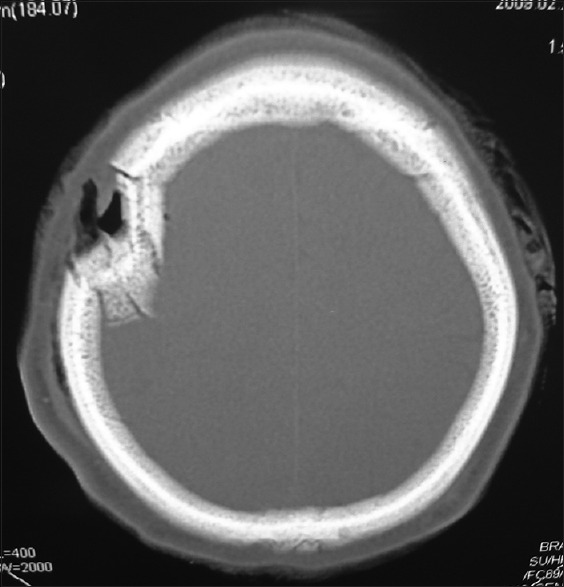

A 34-year-old male with depressed fracture in the right frontal bone with external break in skin integrity with no significant contamination or neurological deficit. CT showed a depressed fracture in the right frontal bone with no underlying parenchymal injury [Figure 3]. This patient was managed conservatively and had a good outcome

Figure 3.

Computerized tomography scan bone window showing depressed fracture or right frontal bone